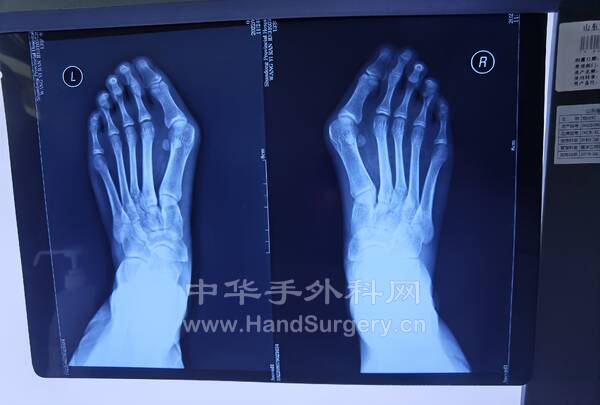

拇趾Chevron+Akin/Scarf+Akin/横行截骨+Akin.第2.3.4趾行Weil手术(图2,3)

3.胫骨延长外固定架术后根据患者情况决定每日拧1圈/2圈,拧3天停1天,1个月复查DR,最终延长的长度以患者行走的舒适度为准!延长的长度约3.5--6cm,外固定架需佩戴4-6个月(图4--7)4.第一,四跖骨短缩的儿童如果想改善外观,可行截骨延长外固定架固定术,需单侧做,时间4-6个月(图8-9)